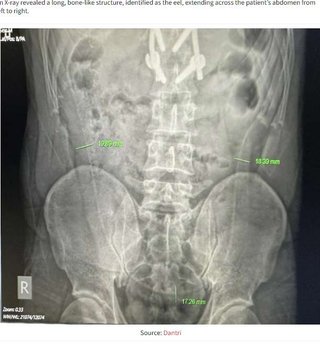

【閲覧注意】激痛で救急外来に駆け込んだ31歳男性、腹腔から長さ65センチのウナギを摘出